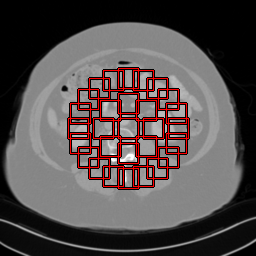

Figure 15: Noise Power Spectrum (NPS) Analysis in comparison to state-of-the-art methods. The x-axis represents normalized frequency in cycles per pixel (px1superscriptpx1\text{px}^{-1}), and the y-axis represents noise power spectrum (HU2px2superscriptHU2superscriptpx2\text{HU}^{2}\text{px}^{2}). Display windows are configured as [1000,800]1000800\left[-1000,800\right] HU. Mean and peak frequencies are intricately linked to noise texture, with finer textures correlating to higher mean and peak frequencies in the NPS. Our method exhibits the highest peak frequencies, indicating that our reconstructed images feature the most refined noise texture among all compared methods.

Figure 16: ROIs for NPS Analysis: Red squares denote 20×20202020\times 20 pixel ROIs distributed evenly across two circular regions. The first circle (radius 252525) holds 888 ROIs, and the second circle (radius 505050) has 202020 ROIs. Both circles, centered at the image center, include a total of 292929 ROIs per image. This standard positioning in the CT community underscores the clinical diagnostic importance of the image center.

We conducted a comprehensive examination of the noise characteristics in our reconstructed images through noise power spectrum (NPS) analysis. NPS serves as a metric, quantifying the magnitude and spatial correlation of noise properties, or textures, within an image. It is derived from the Fourier transform of the spatial autocorrelation function of a zero-mean noise image.

NPS analysis was performed on a configuration of Regions of Interest (ROIs) as depicted in Fig. 16. This process was applied to all 214214214 images from the AAPM test set and for three different views (323232, 646464, and 128128128). The average 1D curves were generated by radially averaging the 2D NPS maps, and the results are presented in Fig. 15.

The area under the NPS curve is equal to the square of the noise magnitude. Importantly, the ordering of methods based on noise magnitude corresponds to the ranking observed in our quantitative experiments for PSNR and SSIM in the main text. For example, FBP, which exhibits the lowest noise magnitude, also performs the poorest in terms of PSNR and SSIM. Conversely, our method, with the highest noise magnitude, stands out as the top performer in both PSNR and SSIM metrics. Furthermore, the mean and peak frequencies serve as key indicators of noise texture or “noise grain size”, where higher frequencies denote finer texture. Remarkably, our method showcases superior mean and peak frequencies compared to other methods, suggesting a finer noise texture or smaller grain size.